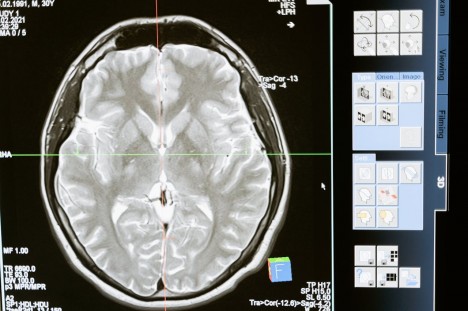

A szellemi alkony első sugarai: a korai demencia felismerése és jelentősége

A demencia nem egyetlen konkrét betegség, hanem egy tünetegyüttes, amely az agyi funkciók fokozatos és visszafordíthatatlan hanyatlását jelzi. Bár gyakran az időskor természetes velejárójának tekintik, a korai szakaszban jelentkező jelek felismerése sorsdöntő lehet a beteg életminőségének megőrzése szempontjából.